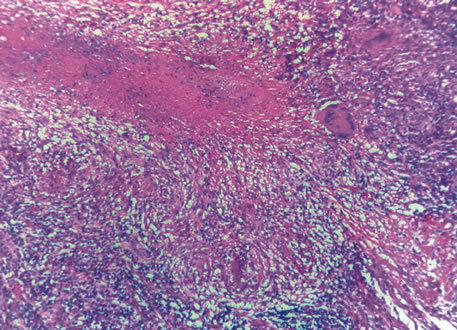

Three histologic patterns of granulomatous inflammation may be seen: diffuse, discrete, and zonal. In diffuse granulomatous inflammation, the epithelioid histiocytes are scattered throughout the involved uveal tissue (Fig. 19). There may be an accompanying background of lymphocytes and plasma cells. Discrete granulomatous inflammation reveals well-circumscribed areas of epithelioid histiocytes (Fig. 20). Zonal granulomatous inflammation consists of a central zone of necrosis and/or polymorphonuclear leukocytes surrounded by epithelioid histiocytes, which is in turn surrounded by a zone of non-granulomatous inflammation consisting of granulation tissue, lymphocytes and plasma cells (Fig. 21).

Fig. 19. Sympathetic ophthalmia. Diffuse granulomatous inflammation involving the choroid. (Hemotoxylin-eosin ×65.)

Fig. 20. Sarcoidosis. Discrete granulomatous inflammation is seen in sarcoidosis. (Hemotoxylin-eosin ×100.)

Fig. 21. Tuberculous choroiditis. A zonal granulomatous inflammation is present. Central area shows necrosis. (Hemotoxylin-eosin ×65.)